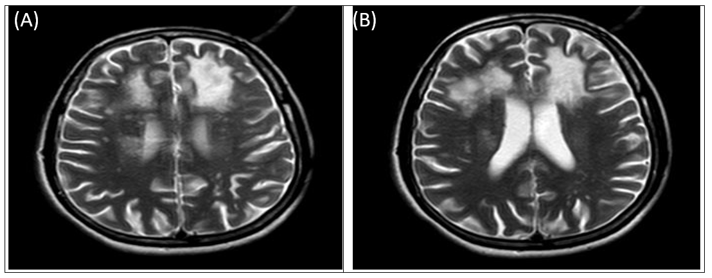

On presentation, the lab investigations revealed a normal biochemistry and hemogram. Patient’s HHH serology was s/o HIV-1 and HIV -2 positive by ELISA and hepatitis B and C were negative. CD4 count was 102/micro litre. Lumbar puncture was done for Cerebrospinal fluid (CSF) analysis which was acellular, total proteins-75 gm, glucose-74, ADA- nil. CSF for cryptococcal antigen, India ink, acid fast bacilli was negative. NCCT head was suggestive of hypo dense lesions in bilateral frontal lobes in the white matter of brain. CEMRI brain with whole spine screening revealed multifocal confluent and discrete areas of T2/FLAIR hyper intensity involving bilateral cerebral white matter with the involvement of subcortical U- fibres at places, midbrain, pons and medulla without diffusion restriction/blooming/enhancement. CSF was found to be positive for John Cunningham VIRUS (JCV) using JCV DNA PCR. Based on the patient’s clinical features, imaging findings, and JCV DNA PCR a diagnosis of PLHIV related Progressive multifocal leukoencephalopathy was made. Patient was started on ART regimen {Tenofovir/Dolutegrevir/Lamivudine} i.e. TLD regimen under NACO guidelines one tablet /day.

Figure 1 Magnetic Resonance Imaging results.

T2/FLAIR: Multifocal confluent discrete areas of hyperintensity involving B/L cerebral white matter.

MRIs of the brain have a high diagnostic value for PML. Single or multiple abnormal signals, round or sector-shaped, can be seen in the periventricular or subcortical white matter, which can be fused with one another and distributed asymmetrically. T2-weighted images and FLAIR reveal hyper intense areas, whereas T1-weighted images reveal hypo intense areas devoid of mass and enhancement. Lesions that extend to the subcortical/juxtacortical white matter are frequently seen on diffusion-weighted images, with peripheral patchy diffusion restriction [5]. Although histopathological evidence is the gold standard for PML diagnosis, the diagnosis is usually suggested by MRI and confirmed by CSF PCR for JCV DNA [6].